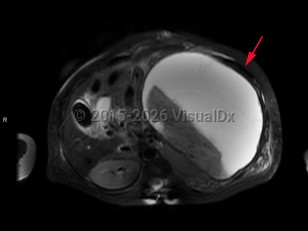

Splenic infarction

A splenic infarction is an ischemic injury to the spleen. It most commonly presents with severe, sharp pain, with a quarter of patients presenting with classic left upper quadrant pain and about half with pain elsewhere in the abdomen; a significant portion have no abdominal pain. Radiation to the left shoulder may sometimes occur, called a Kehr sign. Leukocytosis and fever may also be present. Infarction may lead to rupture, which can cause life-threatening hemorrhage.

Forty percent of splenic infarction cases have more than one predisposing condition, diseases predisposing to embolus, abdominal inflammation, and sickle cell disease. Patients with sickle cell disease are most likely to develop chronic splenic microinfarcts. By the age of 5, these microinfarcts have usually left a patient with sickle cell disease functionally asplenic.